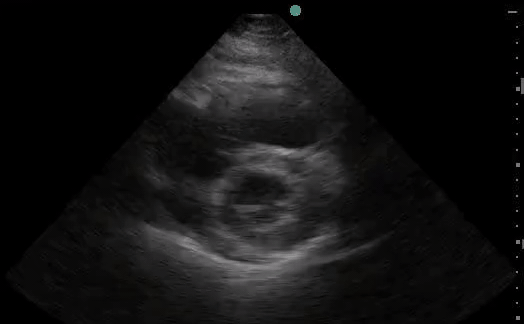

Right Heart Strain

Case 1